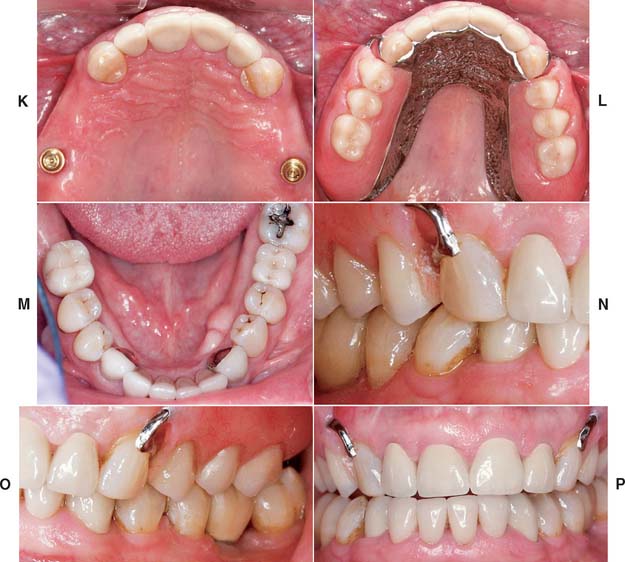

Fig. 32-38 Full-mouth rehabilitation with fixed, implant-supported, and removable partial prosthodontics (Treatment VI). Before treatment: Note the reverse smile line and discrepancy in the maxillary central incisor gingival tissue levels. The maxillary first molars had furcation involvement and poor prognosis as a result of periodontal bone loss. A and B, Occlusal views. C, Frontal view. D and E, Right and left views in maximum intercuspation. F, Diagnostic waxing. G, Dental implants were placed to restore the mandibular arch and provide retention and support for a maxillary partial removable dental prosthesis (RDP). H, The gingival tissue levels were corrected with periodontal surgery. I and J, Anterior teeth prepared for fixed restorations. After treatment: K and L, Occlusal views of maxillary arch with and without partial RDP. M, Occlusal view of restored mandibular arch. N and O, Right and left mirror views in maximum intercuspation. P, Frontal view.

(Courtesy of Dr. B. A. Purcell.)